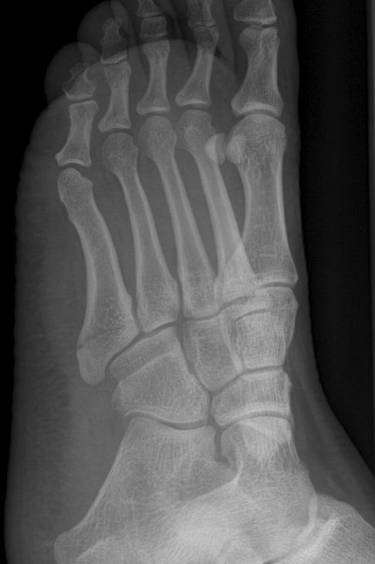

Jones骨折

第5跖骨基底部骨折,累及关节。